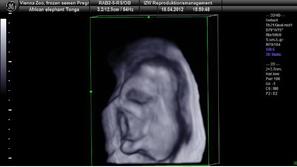

Dunaj Uspešno oplodili slonico V dunajskem živalskem vrtu so uspešno oplodili slonico. Zarodek je trenutno star devet mesecev.